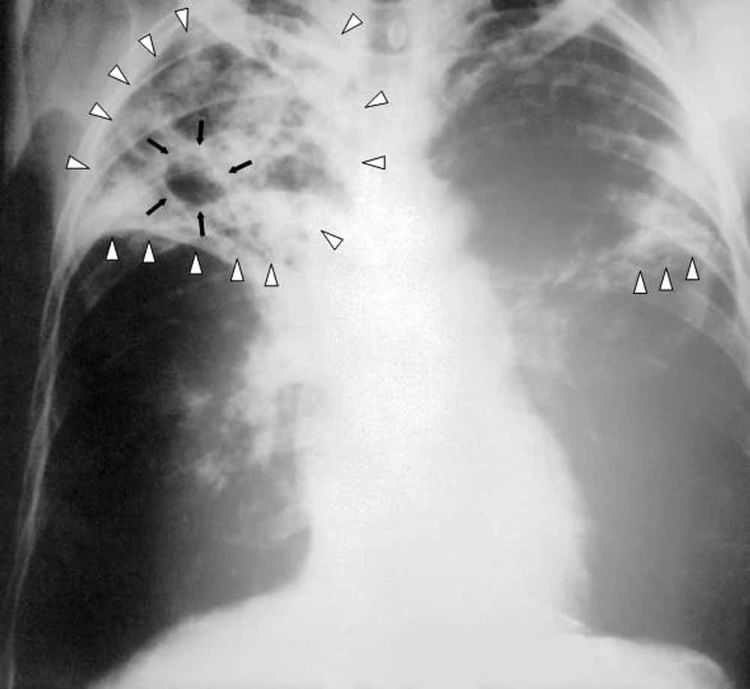

7. Пневмония

Обычная простуда в Средневековье легко могла закончиться смертью.

Пневмония вызывала сильную лихорадку, боли в груди и затруднённое дыхание. Иногда пациенты кашляли кровью.

Проблема была в том, что её часто путали с другими болезнями, включая чуму, и лечили наугад.